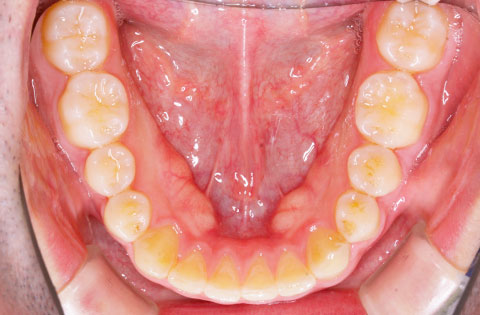

矯正前 下顎

矯正後 下顎